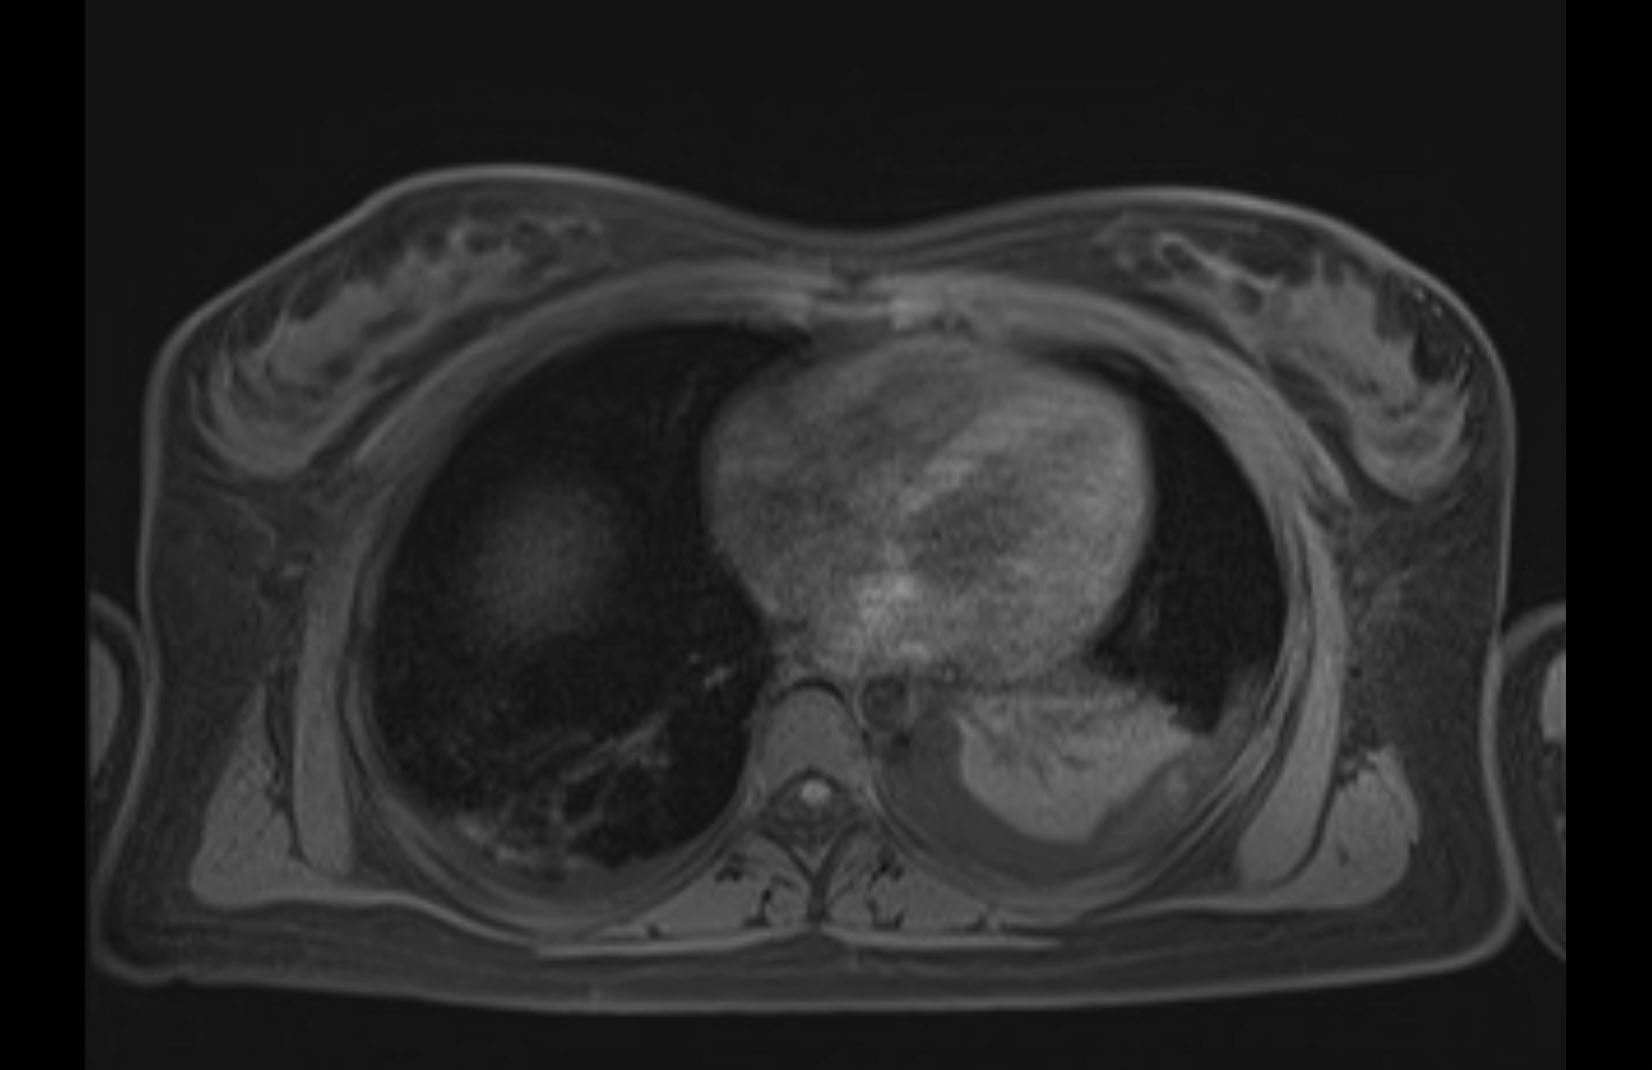

MRI T2